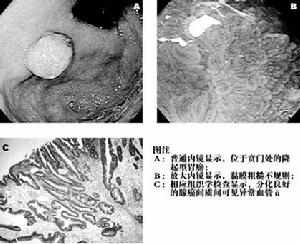

2.胃鏡檢查可見黏膜下腫塊的特徵:腫瘤表面的黏膜呈半透明狀,中央可出現臍樣潰瘍。如腫瘤較大,腫物周圍的橋形皺襞不及良性平滑肌瘤明顯,腫塊邊界不清楚,出現粗大皺襞甚至胃壁僵硬。胃鏡活檢時應儘可能向黏膜深部鉗取,以獲得較高的陽性診斷率。

2.組織學特徵腫瘤細胞呈梭形,與正常的平滑肌有些相似,胞漿較豐富,細胞核位於中央,呈卵圓形或棒狀,染色質粒粗,可見核仁。但腫瘤細胞數多而密集,明顯異形性,核呈多形性,核巨大而濃染或大小形狀不等,核仁粗大,可見多核巨細胞,核分裂象多見。瘤細胞呈束狀及編織狀排列。腫瘤間質較少,有玻璃樣變及黏液變性